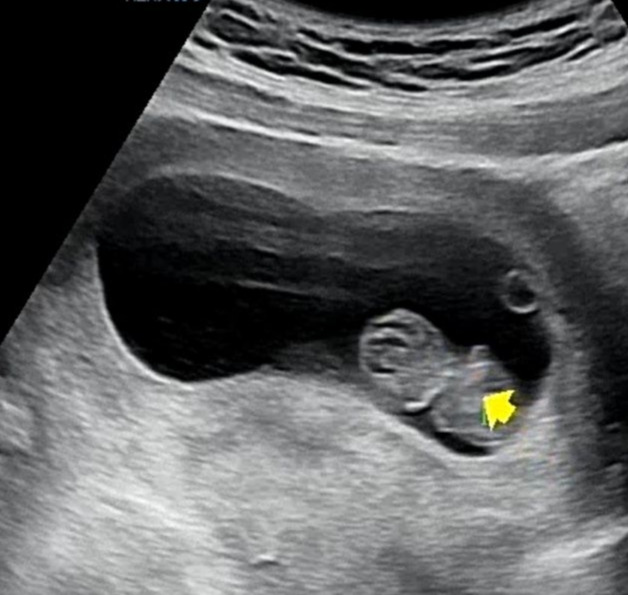

딸은 신랑이 조금이라도 믿음을 주지 않았으면 아이는 없어도 그만이라고 생각했다고 한다. 사위는 누가 봐도 믿음직스러웠고 이 젊은 부부는 아이를 가졌다. 아이의 태명은 딸기였다. 사위의 본가가 논산이라고 하면 사람들은 딸기는 실컷 먹겠다는 소리를 했다. 나는 그게 무슨 소리인가 했는데 논산이 딸기의 고장이었다.

딸은 그냥 딸기를 먹다 지은 태명이라고 했다. 아기 딸기는 아주 작은 씨앗처럼 보이는 초음파 사진에서도 너무 귀여웠다. 어이없을 만큼 귀여웠다. 그 귀여움이 낯설었다.